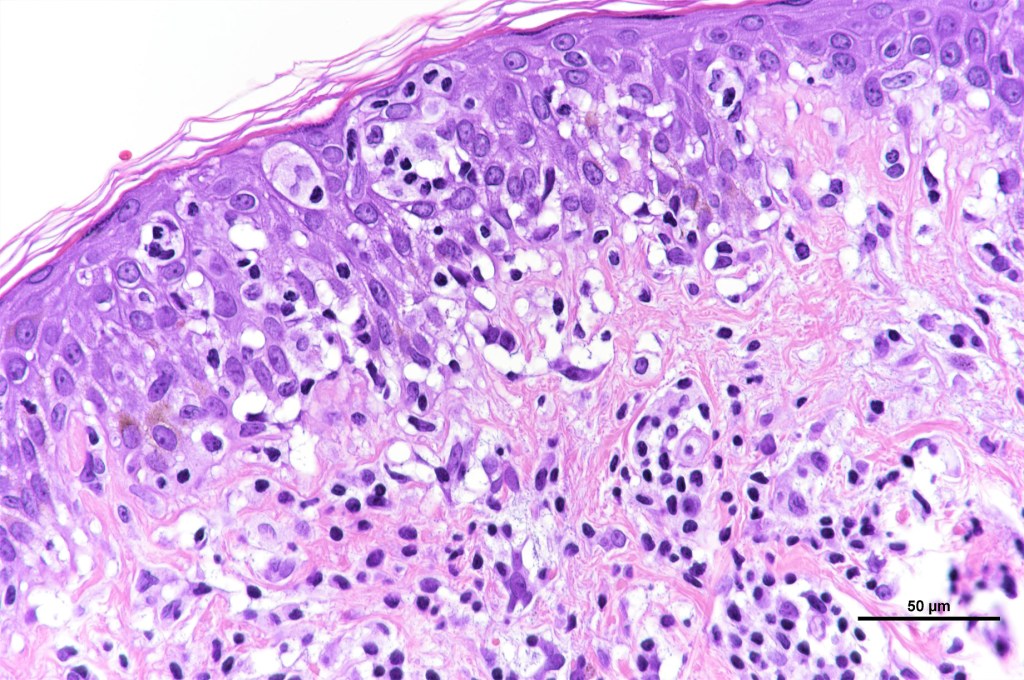

•Type A: 75-80%, wedge shaped infiltrate with base uppermost, large, anaplastic cells with abundant cytoplasm and vesicular nuclei containing prominent nucleoli, can resemble Reed-Sternberg cells, conspicuous mitoses & background infiltrate of lymphocytes, plasma cells, histiocytes, neutrophils & eosinophils

•Variable epidermal necrosis, epidermotropism, edema, hemorrhage & vasculitis/thrombosis